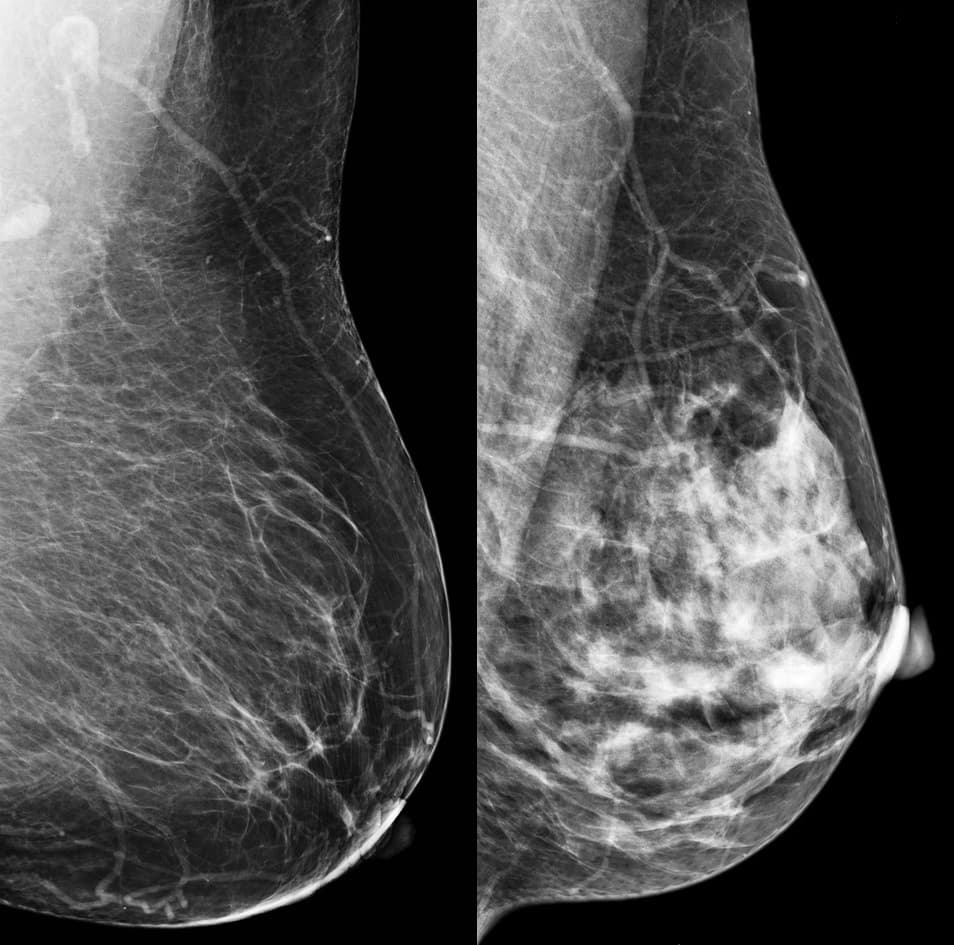

En estas pruebas, el tejido mamario denso se ve blanco, el mismo color que tumores o masas en los senos, lo que hace que sean menos precisas en mujeres con alta densidad.